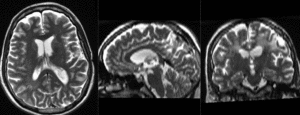

| baseline to T2 after affine+nonrigid alignment (click to enlarge) | |

- the strong EPI-based distortions of the DTI image make nonrigid registration necessary

- initial alignment & overlap is sufficient so that no "initialization" methods are necessary and registration can succeed without.